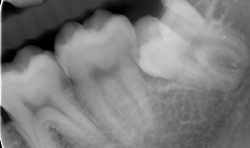

Different thin metallic blades may be connected to the Magnetic Max handpiece, sending a magnetic wave on the tip. The Magnetic Max imparted to blade a longitudinal movement along the central axis, moving up and down between root surface and lamina dura of the alveolus in a repetitive circumferential fashion, providing a driving mechanism of longitudinal movements. This movement also allows the maintenance of lamina dura for wisdom teeth (Figs. 4a-4c).

Fig. 4b

Fig. 4c